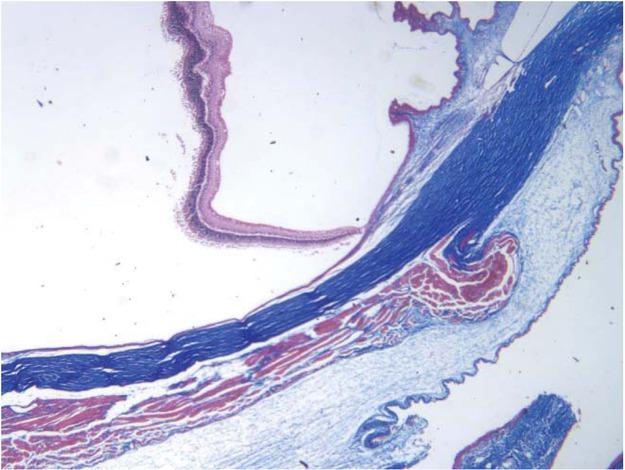

Fig. 7 shows sections of an eye stained with Masson stain. The sections were from an eye into which bevacizumab was delivered from the “tracer-gel”. The sections are useful for orientation, with collagen stained blue (cornea, sclera) and neural retina, epithelium and muscle stained crimson. The embedding and sectioning procedures have caused the retina to be dislodged from its normal position in contact with the sclera.

Masson-stained section of a posterior area of a rabbit eye into which bevacizumab was delivered from the “tracer-gel”. The sclera is stained bright blue and the retina, epithelia and muscle stained crimson. The retina and choroid have separated from the sclera.

Masson-stained section of the limbal region of a rabbit eye into which bevacizumab was delivered from the “tracer-gel”. The sclera and cornea are stained bright blue and the retina, epithelia and muscle stained crimson. The retina and choroid have separated from the sclera.